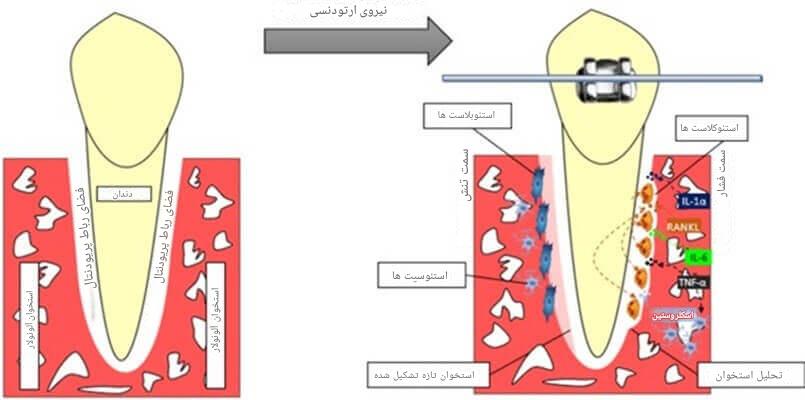

فرآیند بیولوژی حرکت دندان در ارتودنسی با اعمال نیرویی خفیف اما مداوم از سوی ابزارهای ارتودنسی آغاز میشود. این نیرو باعث میشود دندان به یک سمت حرکت کند و همین موضوع منجر به ایجاد دو ناحیهی متمایز در اطراف آن میشود: ناحیهی فشار (سمت حرکت دندان) و ناحیهی کشش (سمت مقابل). ساختاری به نام لیگامان پریودنتال (رباط نگهدارنده بین ریشه دندان و استخوان فک) مستقیماً تحت تأثیر این تغییر قرار میگیرد و به صورت فشرده یا کشیده درمیآید.

در عرض چند ساعت، بدن نسبت به این تغییرات واکنش نشان میدهد. سلولهای موجود در رباط که توانایی حس نیروی مکانیکی را دارند، تغییرات فشار را دریافت کرده و سیگنالهای بیوشیمیایی ترشح میکنند. این سیگنالها، جریان خون را در بافتها تغییر داده و باعث آزاد شدن پیامرسانهای سلولی اولیه میشوند. این مرحلهی اولیه، آغازگر فرایندهای سلولی پیچیدهتری است که در مراحل بعدی، مانند تحلیل استخوان و ساخت مجدد آن به آنها خواهیم پرداخت. در واقع، پشت این فشار ساده بریس، زنجیرهای هدفمند از واکنشهای بیولوژیکی است که بدن آن را نه بهعنوان آسیب، بلکه بهعنوان یک تغییر قابل تطبیق میپذیرد.

در ناحیهای که دندان به آن سمت حرکت میکند، PDL بهشدت فشرده میشود؛ این فشردگی در عرض ۴۸ تا ۷۲ ساعت باعث کاهش جریان خون موضعی میشود. در مقابل در سمت دیگر رباط، کشش ایجاد شده باعث افزایش جریان خون و گشاد شدن عروق میشود. این تغییرات باعث فعالیت سلولهایی چون فیبروبلاستها (سازنده بافت همبند) و ماکروفاژها (سلولهای ایمنی پاکسازیکننده) میشود.

پس از آمادهسازی محیط توسط لیگامان پریودنتال، یکی دیگر از پاسخهای بیولوژیکی بدن به ارتودنسی مربوط به استخوان فک است تا پاسخ سازگاری خود را آغاز کند. استخوان آلوئول (بخشی از فک که دندانها را نگه میدارد) ساختاری زنده و پویاست که در پاسخ به تحریک مکانیکی، ساختار خود را بازسازی میکند. این مرحله حیاتی، حدود ۳ تا ۵ روز پس از اعمال نیروی ارتودنسی آغاز میشود.

در ناحیهی فشاری، سلولهایی به نام استئوکلاستها فعال میشوند. این سلولها با تجزیهی استخوان موجود، فضا را برای حرکت دندان باز میکنند—فرآیندی که به آن تحلیل استخوانی (bone resorption) گفته میشود. در سوی دیگر، یعنی ناحیه کشش، استئوبلاستها به صحنه میآیند تا با ساخت ماتریس استخوانی جدید، استخوان تازه بسازند— فرآیندی موسوم به استخوانسازی (bone formation).